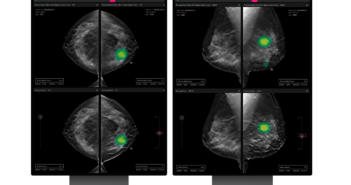

의료 인공지능(AI) 기업 루닛이 3차원(3D) 유방단층촬영술 AI 영상분석 솔루션 '루닛 인사이트 DBT'가 미국 식품의약국(FDA)으로부터 시판 전 허가(510(k) Clearance)를 받았다. 510(k)는 FDA가 의료기기 안전성과 유효성을 검증하는 제도로, 국내 3차원 유방암 검출 AI 솔루션이 FDA 허가를 획득한 것은 이번이 처음이다. 루닛 인사이트 DBT는 유방단층촬영술(DBT)의 3차원 영상을 AI 기반으로 분석해 의료진의 유방암 진단을 보조하는 제품이다. 특히 기존 2차원 유방촬영술에 비해 더 빠르고 정확한 진단을 제공한다는 점에서 미국 등 선진국에서 수요가 높다. 이번 FDA 인증에 따라 루닛은 미국에 본격 진출하게 됐다. 앞서 루닛은 지난 2월 유럽 자회사 '루닛 유럽 홀딩스'를 설립하고, 미국에 이은 거대시장 유럽에 루닛 인사이트 DBT를 출시한 바 있다. 또한 같은달 열린 유럽 최대 영상의학회 ECR 2023에서 루닛 인사이트 DBT 관련 연구가 학회 주요 연구인 구연발표(Oral PT)로 채택됐다. 서범석 루닛 대표는 "미국과 같은 의료 선진 시장에서는 이미 유방촬영술을 통한 2차원 검진을 뛰어 넘어 3차원 유방단층촬영술 방식이 대세로 자리잡았다"며 "미국 의료기관들이 유방암 정밀진단에 대한 수요가 높다는 점을 감안해 현지 의료기관을 대상으로 정확도 높은 AI 솔루션에 대한 영업·마케팅 활동을 강화하고, 시장을 신속히 확대해 나갈 것"이라고 말했다. 관련 기사 더보기 https://www.venturesquare.net/902560